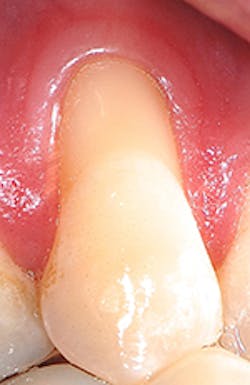

"Recession of the gingiva is becoming a prominent condition in the oral health of many patients and should be treated at its earliest detection," according to A.P. Saadoun in "Current trends in gingival recession coverage - Part I: the tunnel connective tissue graft."5 Saadoun also says the ideal time to correct gingival recession is at a Class I-II, which is less traumatic surgically for the patient, and which achieves predictable regenerative results (see Figures 1, 2).